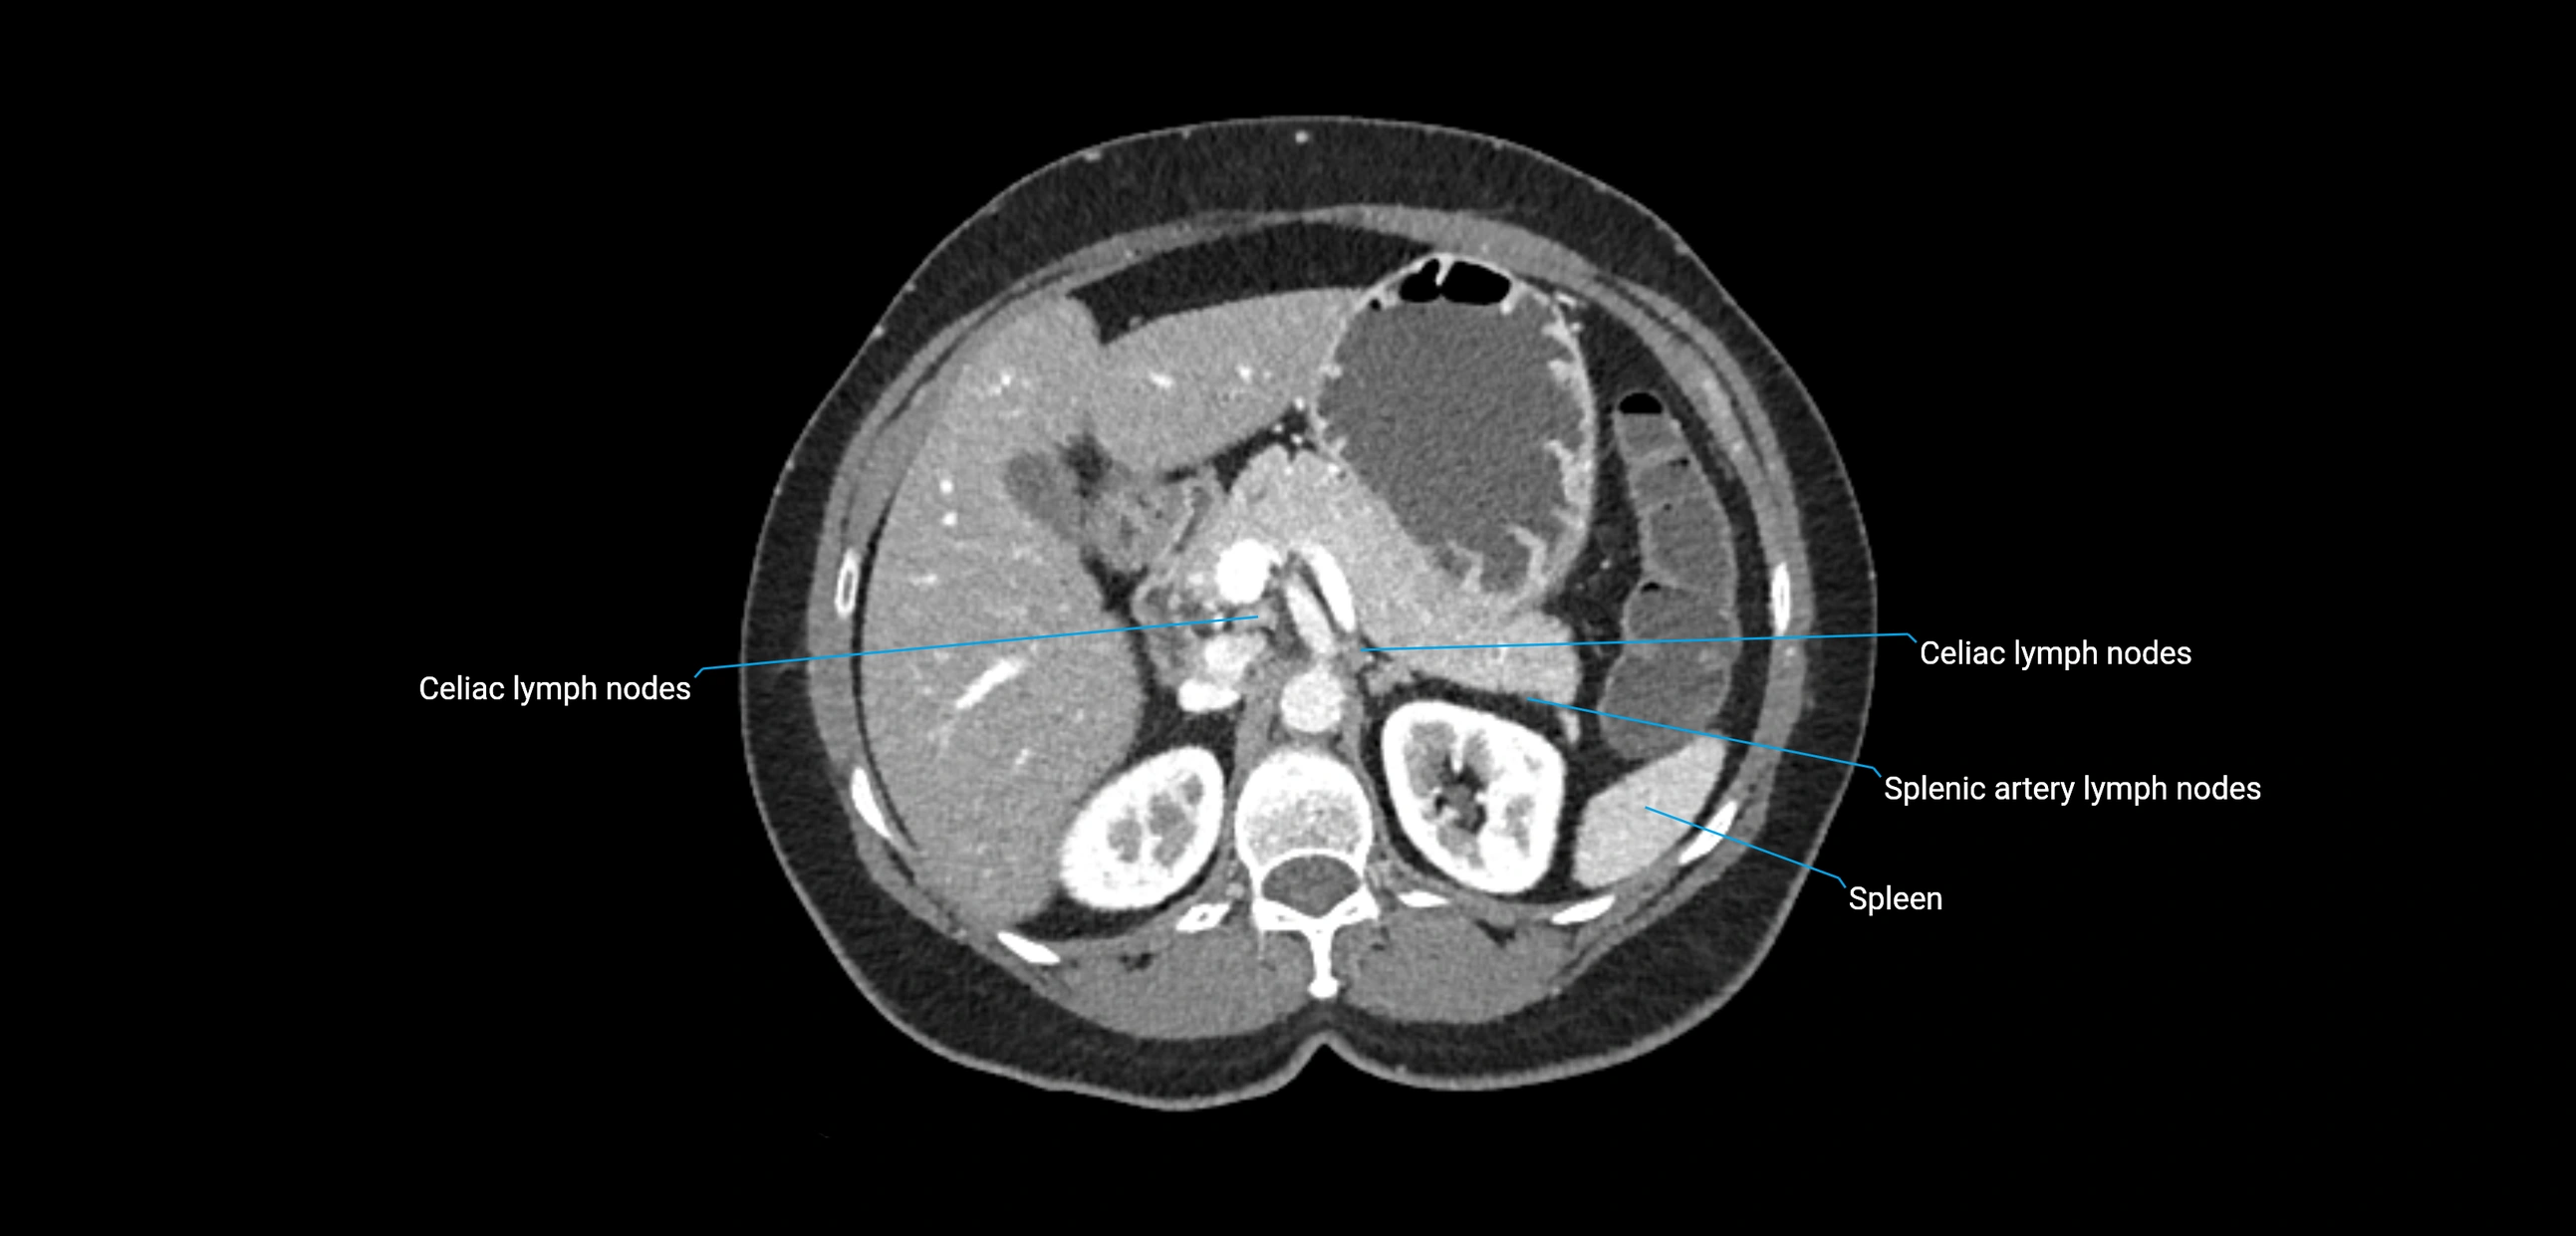

CT Appearance

CT Pre-Contrast:

• Nodes appear as soft-tissue density nodules adjacent to the aorta and IVC

• Calcification may be seen in chronic infections (e.g., tuberculosis)

CT Post-Contrast:

• Normal nodes enhance homogeneously

• Malignant nodes may show heterogeneous enhancement, central necrosis, or conglomerate formation

• Size >1 cm short axis is suspicious, though morphology and distribution are equally important

CT Venography (CTV):

• Demonstrates nodal encasement or compression of adjacent vessels (aorta, IVC, renal veins)

• Useful in staging testicular and ovarian malignancies

• Provides 3D reconstructions for retroperitoneal lymph node dissection planning

CT image

image